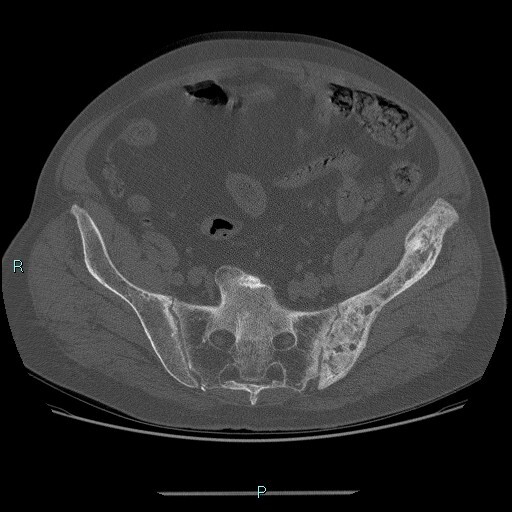

Welche Pathologie erklärt am ehesten die Veränderungen des linken Hemibeckens auf dem vorliegenden CTs eines 80-jährigen Patienten?